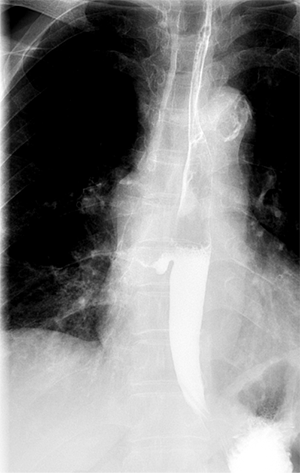

为了进一步验证我们的猜想,我们对李大娘进行了碘造影剂的上消化道造影检查,可见造影剂通过食管胸下段向右侧流入纵膈内,最终流入右下叶支气管内,患者出现明显呛咳,这让我猜想的食管下段纵膈、气管瘘诊断明确了。此后的增强CT检查也证实了这一点,至此,困扰了李大娘十余年的“怪病”终于找到了原因。李大娘万万没想到,查了这么多年的肺病,病根竟在食管上。